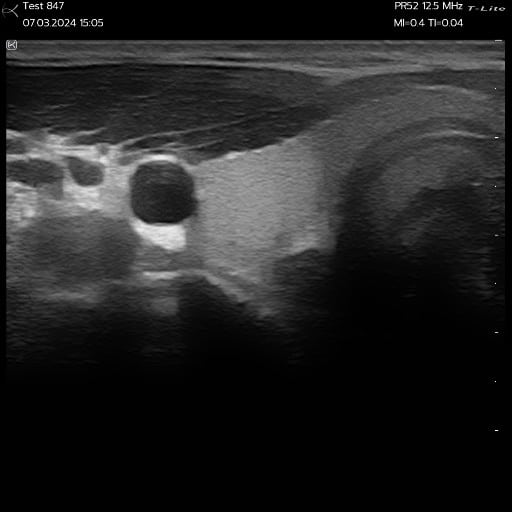

L’image qui apparaît sur l’écran présente alors des zones plus sombres, allant du gris foncé au noir selon le degré d’hypoéchogénicité. Cette différence de contraste aide le praticien à localiser et délimiter la lésion lors de l’examen échographique.

Nodules thyroïdiens observés avec un échographe ultraportable Sonoscanner

Les kystes simples sont l’exemple type de structures hypoéchogènes. Ils peuvent se situer dans le foie, les reins ou les ovaires. Ces kystes contiennent un liquide homogène qui apparaît en gris foncé ou noir à l’échographie. Leur paroi fine et leurs contours nets permettent de les distinguer des lésions solides.

Certains nodules thyroïdiens présentent également une hypoéchogénicité. Ce phénomène peut se retrouver aussi bien dans les adénomes bénins que dans les carcinomes. Le score TI-RADS prend en compte l’hypoéchogénicité comme critère de suspicion, sans que ce signe soit spécifique de malignité.